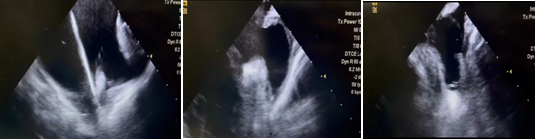

此例手术由韩稳琦博士和酉鹏华博士通过ICE指导下进行,通过ICE精准构建心脏模型、直视下穿刺房间隔,结合三维标测系统,精准、高效地完成双侧肺静脉隔离。后通过ICE及左心耳造影评估左心耳特征为下缘短,上缘折角大的短颈鸡翅型心耳,利用12F导引系统鞘管和猪尾导管在DSA肝位下同时造影,测量左心耳开口25.12mm,最大可用锚定区深度19.71mm,最终选择31mm规格watchman FLX封堵器的植入。ICE从不同角度检查即将释放的WATCHMAN FLX左心耳封堵器,观察封堵器位置、露肩、残余分流和压缩比情况,明确封堵器位置合理,无明显露肩,完全封堵无残余分流,封堵器位置良好。随后在ICE下观察及DSA透视下作牵拉试验,直到最后一次牵拉与前一次牵拉比较无位置改变,压缩比无明显变化,符合封堵器释放的“PASS”原则后完全释放封堵器。

1 ICE观察测量左心耳开口及深度

3 术后ICE观察测量Watchman FLX封堵器位置